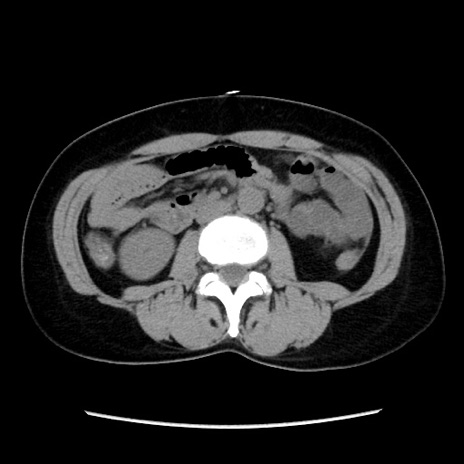

症例10(横断像)

【症例】 50歳代女性

【主訴】 腹痛

【現病歴】前日生レバーを食べた。今朝に排便あり。 昼前に突然発症の腹痛を生じ、当院救急外来を受診した。

【既往歴】 子宮筋腫にてで子宮全摘後

【身体所見】 意識清明、腹部:平坦、軟、下腹部やや左を中心に圧痛・反跳痛あり、筋性防御あり

【データ】WBC 7800、CRP 0.07